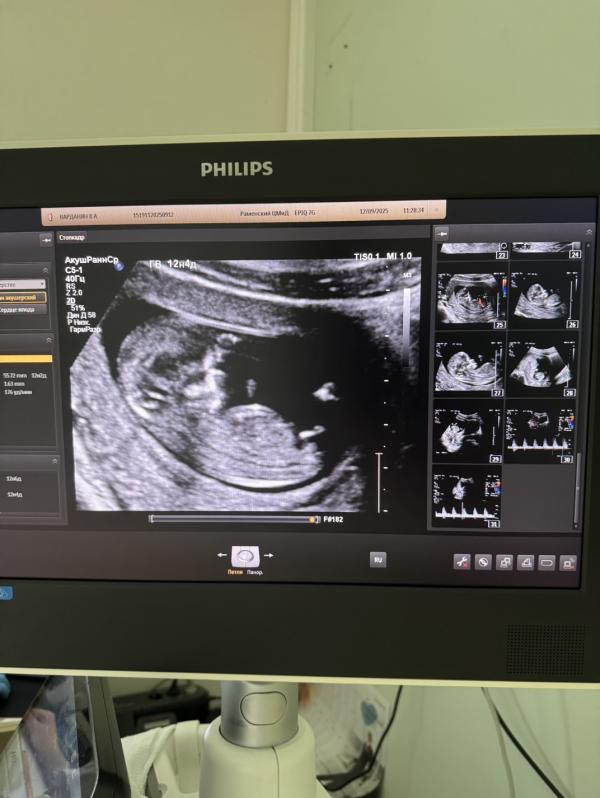

1 скрининг - как думаете мальчик или девочка? 🥰Сделала наконец-то 1 скрининг, очень переживала, так как он самый важный

Какой красивый малыш😻Как будто мальчик , но это не точно))

Да тоже по чертам будто бы мальчик, но не знаю не знаю 😁

Девочка)